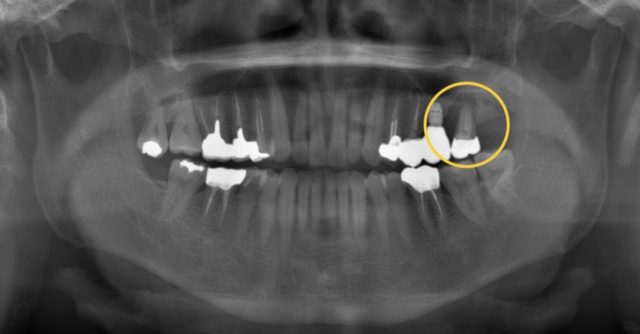

この方は左上の1番奥の歯を、自費で根管治療を行い、合わせて手前にはインプラントを入れたそうです。

お口全体のレントゲンとCTを診てもらうと、歯を支えている骨がゴッソリ溶けていました、、、

ここまで溶けているともう抜歯しか選択肢はありません😨

お金をかけて治療したのに抜歯になってしまい、とても落ち込んでいました。